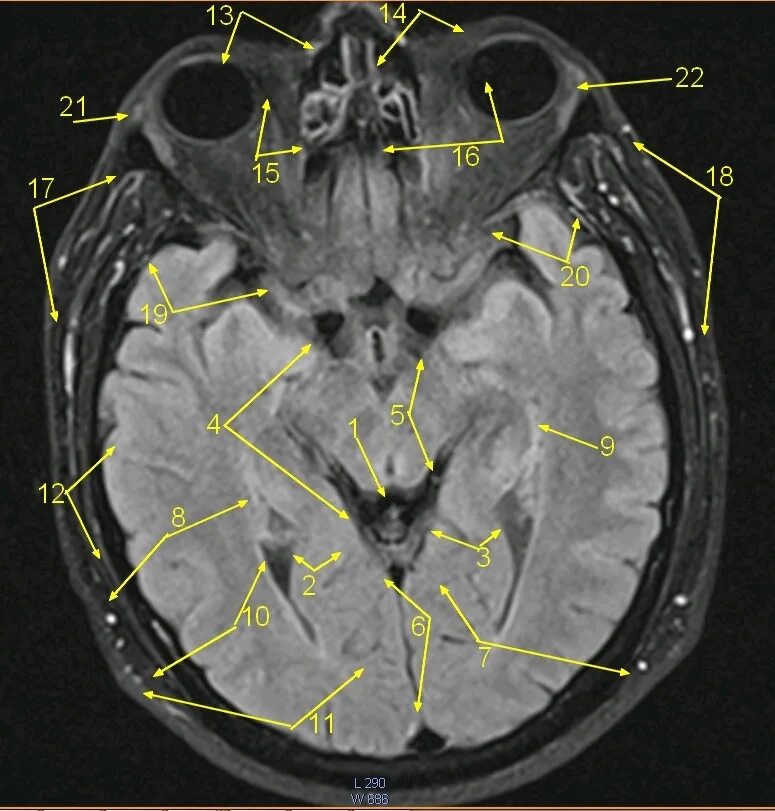

Цистерны на кт